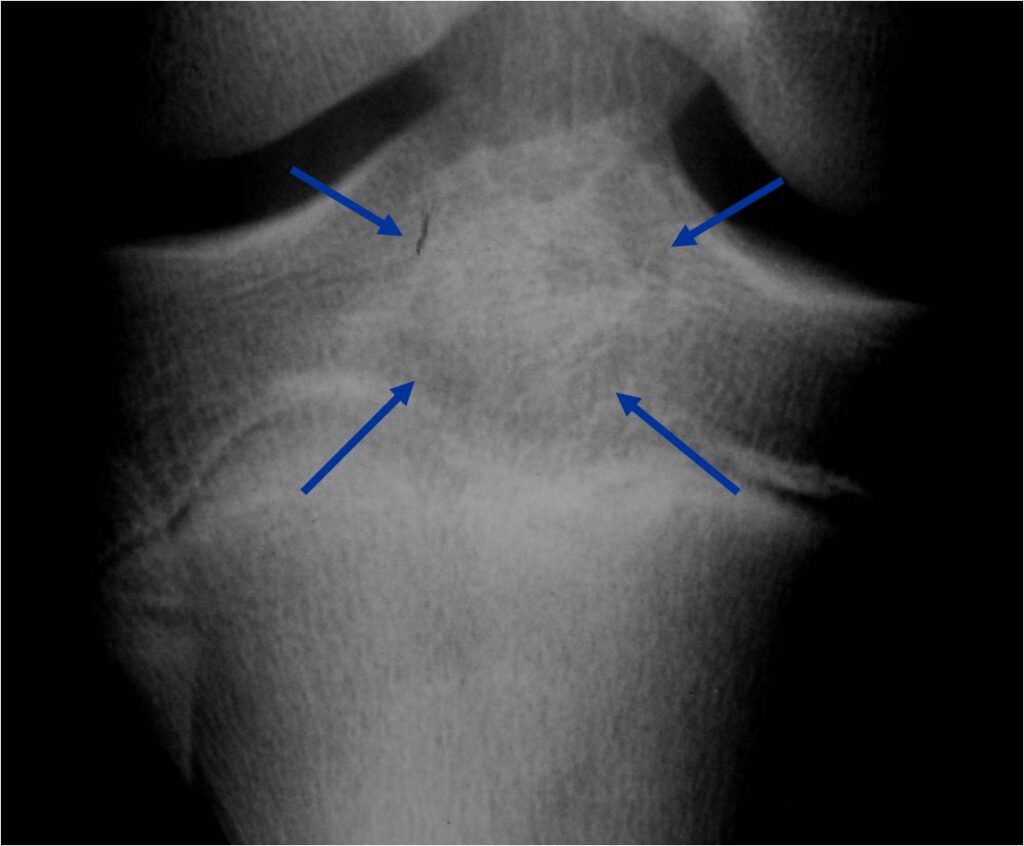

- (MRI appearance)

- Geographic, well circumscribed lesion in the epiphysis

- Intermediate Signal on T1

- High signal on T2 mixed with low signal areas (low signal areas proposed to be secondary to lysosomal content of highly cellular areas)

- Fluid/Fluid levels demonstrated in tumors that have undergone ABC change (aneurysmal bone cyst change)

- Extensive Surrounding edema is common

- Joint effusion in 30-50% of cases